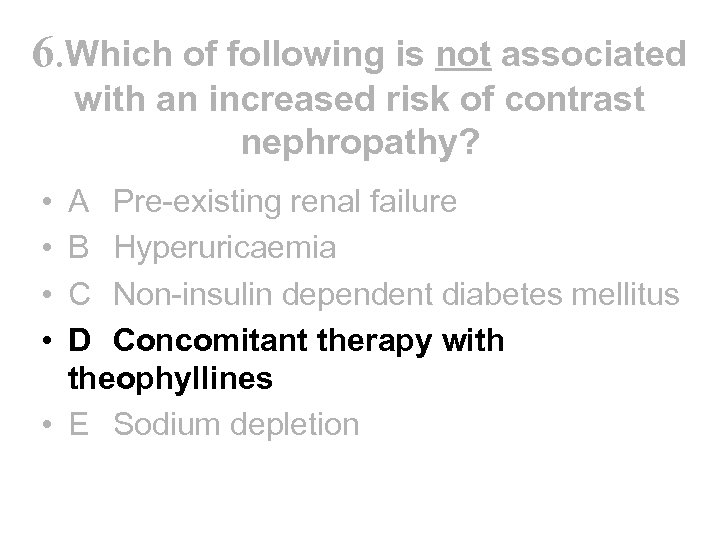

6. Which of following is not associated with an increased risk of contrast nephropathy? • A Pre-existing renal failure • B Hyperuricaemia • C Non-insulin dependent diabetes mellitus • D Concomitant therapy with theophyllines • E Sodium depletion

6. Which of following is not associated with an increased risk of contrast nephropathy? • A Pre-existing renal failure • B Hyperuricaemia • C Non-insulin dependent diabetes mellitus • D Concomitant therapy with theophyllines • E Sodium depletion

6. Which of following is not associated with an increased risk of contrast nephropathy? • • A Pre-existing renal failure B Hyperuricaemia C Non-insulin dependent diabetes mellitus D Concomitant therapy with theophyllines • E Sodium depletion

6. Which of following is not associated with an increased risk of contrast nephropathy? • • A Pre-existing renal failure B Hyperuricaemia C Non-insulin dependent diabetes mellitus D Concomitant therapy with theophyllines • E Sodium depletion